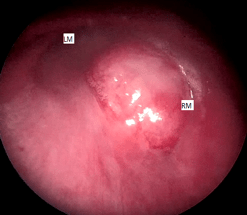

ผู้ป่วยได้รับการส่องกล้องหลอดลมชนิดแข็ง (rigid bronchoscopy) ร่วมกับการทำ tumor removal โดยวิธี multimodality techniques ได้แก่ Nd-YAG laser เพื่อ devitalized tissue และป้องกันการเกิดเลือดออก, forceps debulking และ mechanical coring out หลังจากการทำหัตถการสามารถเปิด right main bronchus ได้ แต่ยังมี residual tumor ที่ posterior wall ของ right main bronchus ดังแสดงในรูปที่ 4 ผลการตรวจทางพยาธิวิทยาพบเป็น benign nerve sheath tumor favor schwannoma (positive for S100, SOX10 และ vimentin และ negative for HMB 45, melan A, AE1/AE3, CD56 และ EMA)

รูปที่ 4 ภายหลังการทำ tumor removal; A, Residual tumor ที่ posterior wall ของ right main bronchus และพบมี carinal involvement; B, Right bronchus intermedia ไม่พบ tumor involvement; LM, left main bronchus; RM, right main bronchus; RBI, right bronchus intermedia; RML, right middle lobe; RLL, right lower lobe.